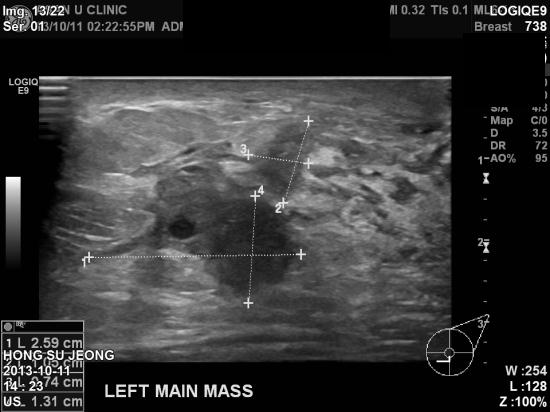

본원에서 재 시행한 정밀초음파상 좌측 유방의 혹이

유두 안쪽으로 퍼진상태였고

좌측겨드랑이 임파절에도 전이소견

보였습니다